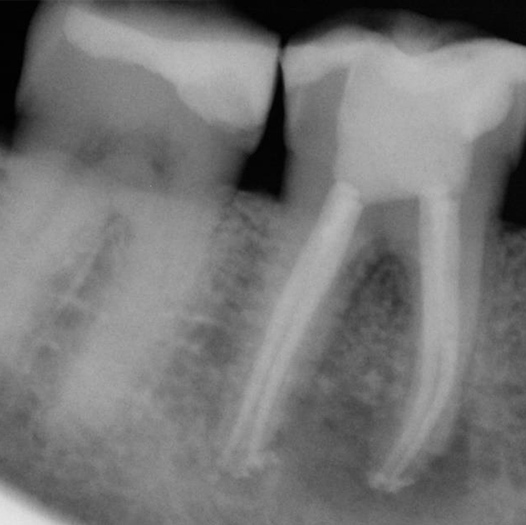

After

After Root Canal treatment